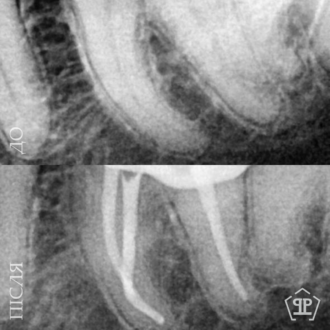

Перелечивание корневых каналов. Пациент обратился с признаками воспалительного процесса в верхнем зубе. Выявлены незапломбированные корневые каналы. Выполнен тщательное перелечивание с последующим герметическим пломбированием.

Перелечивание корневых каналов. Пациент обратился с симптомами, свидетельствующими о недостаточном предварительном лечении. Выполнены перечисления корневых каналов, тщательная очистка и повторная пломбировка для достижения полной герметичности и предотвращения рецидива воспаления.

Первичное лечение корневых каналов. Лечение пульпита, возникшего вследствие глубокого кариеса.